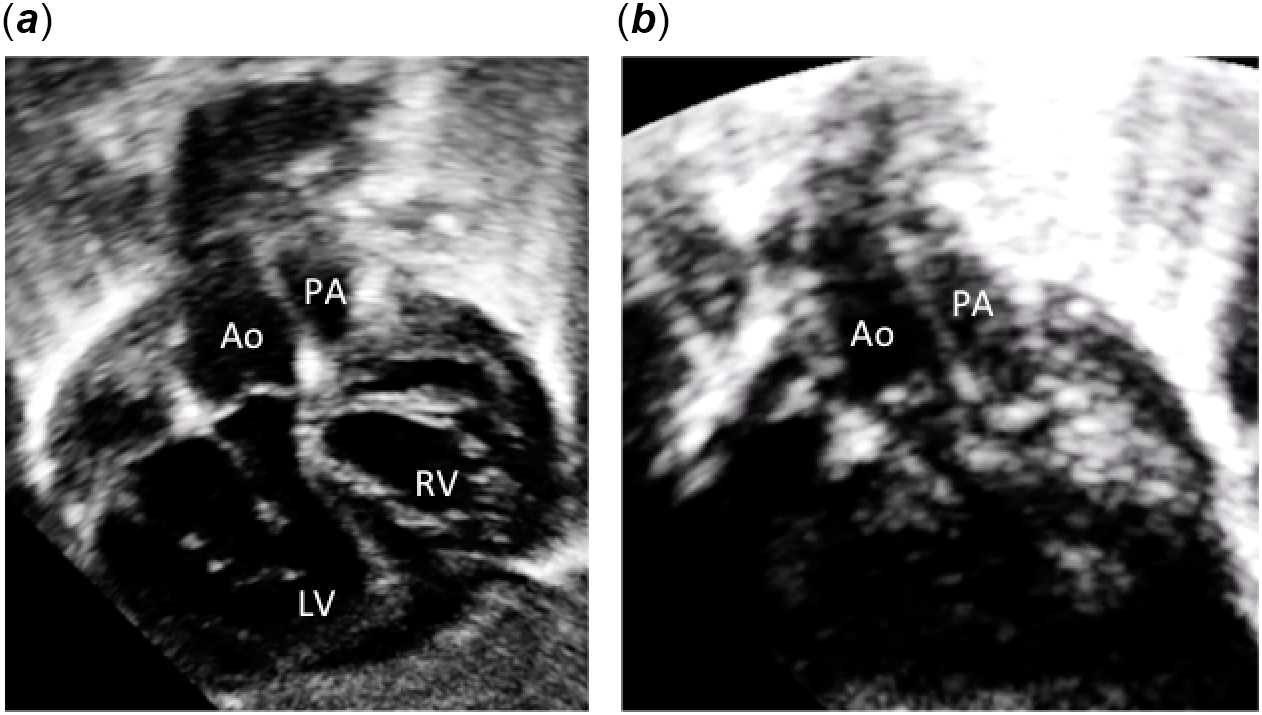

A full-term female neonate with a prenatal diagnosis of “ventricular inversion” was admitted, at birth, to the neonatal ICU with profound cyanosis. Two-dimensional colour Doppler echocardiography showed levocardia, situs solitus of the atria, and discordant atrioventricular connections with l-loop of the ventricle (Fig 1a and c). The ventriculoarterial connections were concordant with the aorta arising anteriorly and right-sided from the right-sided morphologically left ventricle (Figs 1b, 2a and b). The pulmonary artery arose posteriorly and left-sided from the left-sided morphologically right ventricle (Fig 2a). The two great arteries are parallel to each other without spiralisation (Fig 2b). There was a small interatrial communication that required a Rashkind procedure at 3 days of age. The ventricular septum was intact (Figs 1a and 2a). The diagnosis of anatomically corrected malposition of the great arteries [S,L,D] was done, and the patient underwent a successful Mustard operation at 5 months of age. No extracardiac anomalies were detected clinically and by cerebral and abdominal ultrasound examinations.

Figure 2. Subcostal two-dimensional echocardiographic pictures. (a) Subcostal view showing ventriculo-arterial concordance. The aorta arises anteriorly from the right-sided morphologically left ventricle and the pulmonary artery arises posteriorly from the left-sided morphologically right ventricle. (b) Subcostal view showing the short sub-aortic and sub-pulmonary infundibulum and the parallel position of the great arteries. Ao: aorta; PA: pulmonary artery; LV: left ventricle; RV: right ventricle; RA: right atrium; LA: left atrium.